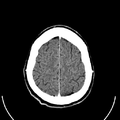

تصوير مقطعي حاسوبي

التصوير المَقْطَعي الحاسوبيX-ray computed tomography نظام تصوير بالأشعة السينية، يُسْتخدم لتصوير مختلف أجزاء الجسم مثل الرأس والقلب والبطن. ويستعين الأطباء بالتصوير المقطعي الحاسوبي على تشخيص الأمراض وعلاجها. وتسمى هذه التقنية أيضًا التصوير المقطعي المحوسب أو التصوير المقطعي المحوري المحوسب.

معرض الصور